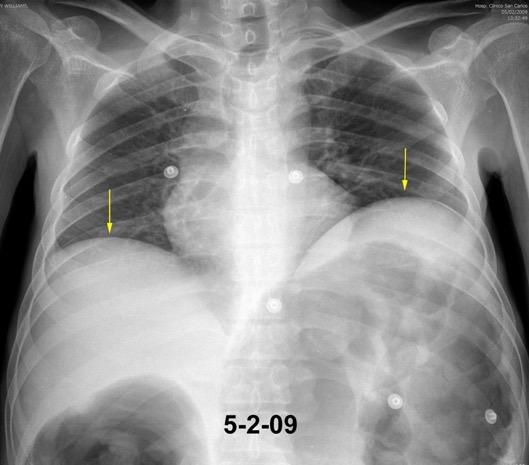

28. ELEVACIÓN UNILATERAL. OBSTRUCCIÓN INTESTINAL

Tromboembolismo pulmonar Diafragma elevado 20%

Rx: Niveles hidroaéreos en hemitórax izquierdo Desviación mediastínica Ausencia de intestino en abdomen. Configuración en reloj de arena del intestino herniado “Tubo nasogástrico”